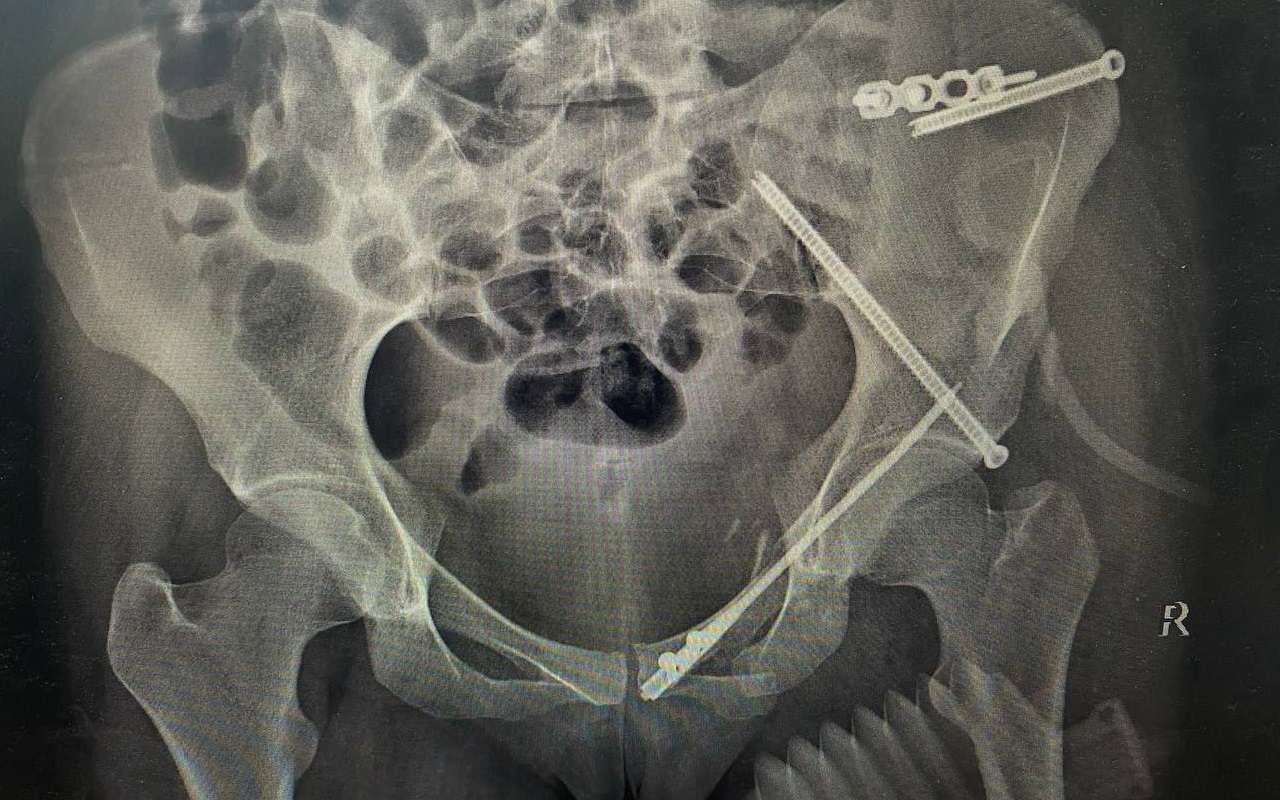

Авария произошла в июне текущего года. Мотоцикл, в котором находилась пострадавшая, столкнулся с автомобилем. В результате ДТП девушка получила множественные закрытые переломы костей таза со смещением отломков. Пациентку экстренно госпитализировали в Борисоглебскую РБ. А позже ее транспортировали в травматологическое отделение БСМП №1 для оказания специализированной медпомощи.

Девушке провели обследование и предоперационное планирование с использованием 3D-моделей. После этого бригада врачей провела операцию по металлоостеосинтезу, когда кости таза фиксируют при помощи винтов и титановых пластин.

Операция прошла успешно. Врачам удалось снизить кровопотерю, уменьшить болевой синдром и надежно зафиксировать кости таза. Во время операции пациентке сделали небольшие надрезы. Это способствует более быстрому сращиванию переломов, а шрамы останутся почти незаметными.